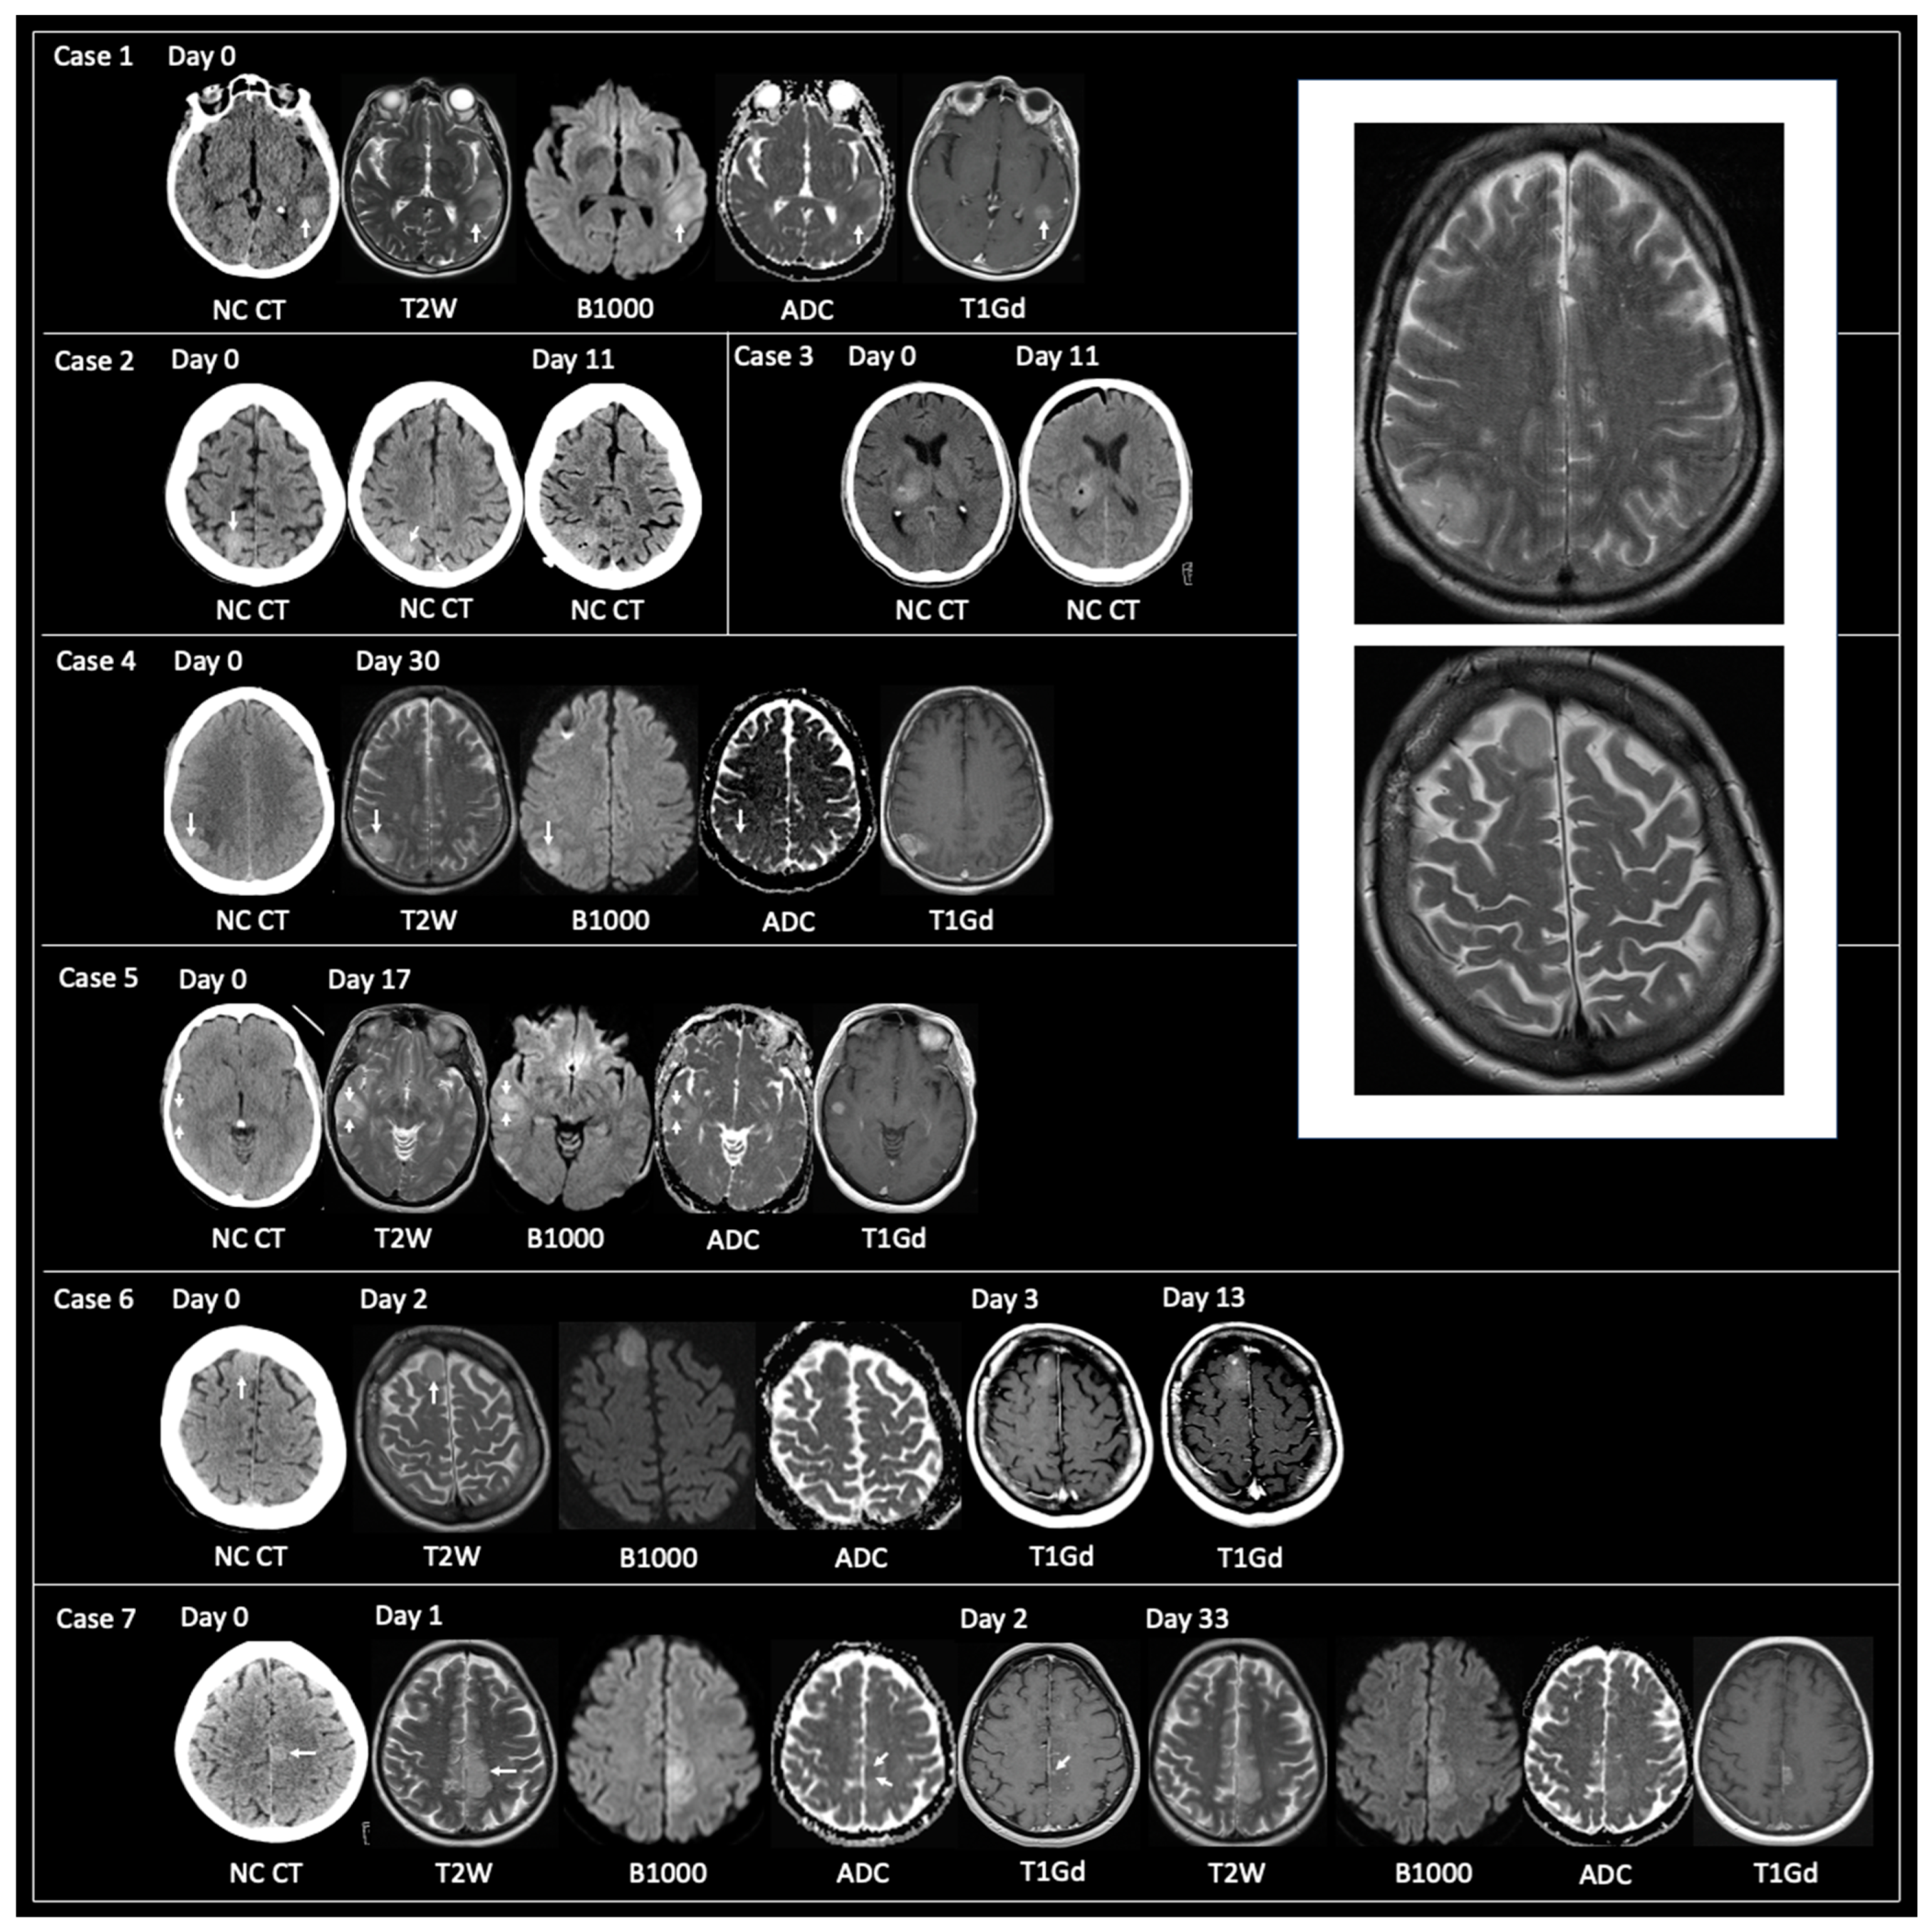

3.1.1. Non-Typical GBM at Time of Tissue Sampling

3.1.2. TRA GBM with Preceding Imaging